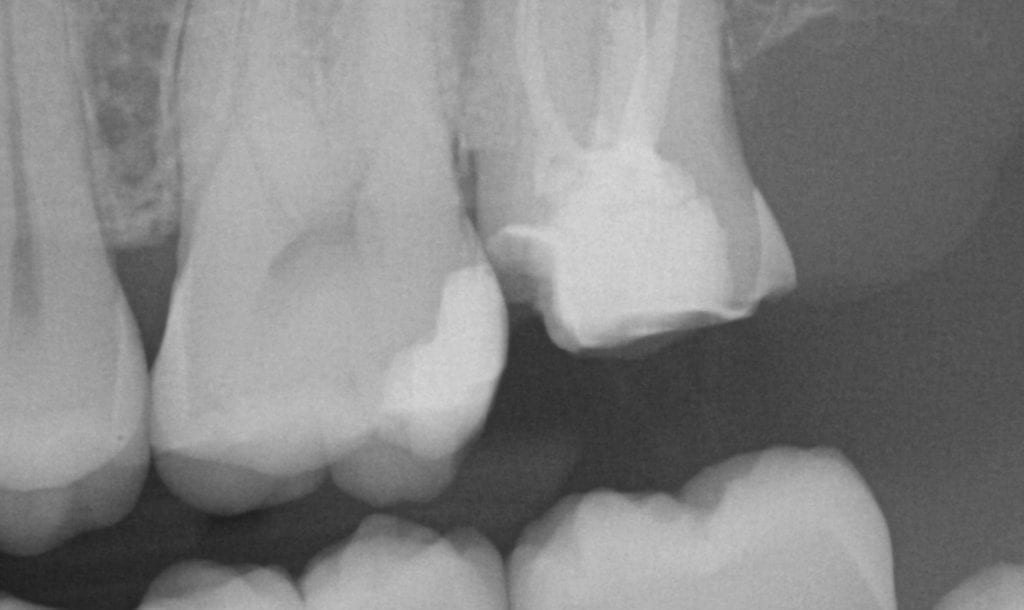

It was a long struggle to find margins with the Omnicam and after 4 years it was sold. The margin definition and resolution never reached an acceptable level. After seeing margins from high resolution scans by the Medit and defining them in exocad, it completely validated that we shouldn’t settle for anything less than the highest standard. This is an scan performed on a upper second molar with tough access, replacing a failing crown.

LAST X-RAY IS IMMEDIATE POST OP- EXCESS CEMENT WAS REMOVED AFTER FILM CHECK